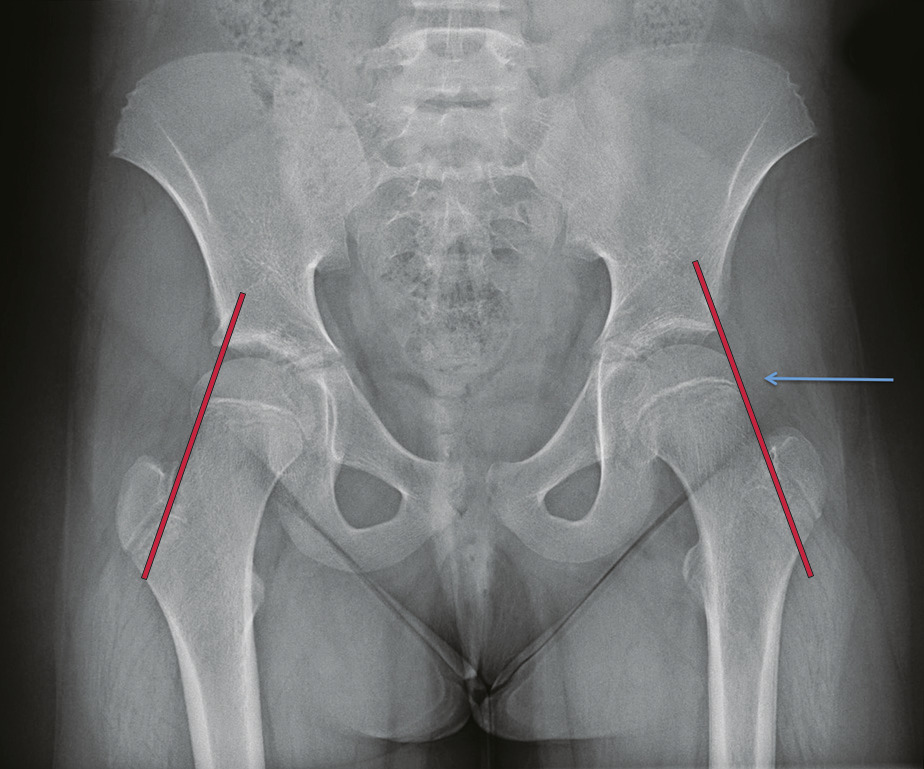

Bascule de la tête fémorale en dedans et en arrière (fig. 1), de cause inconnue, mais liée à une fragilité du cartilage de croissance.

Diagnostic confirmé par radiographie du bassin de face et surtout de profil. En cas de glissement minime : tracer la ligne de Klein, tangente au bord supérieur du col fémoral (elle ne croise plus le pôle supérieur de l’épiphyse ; fig. 1a).